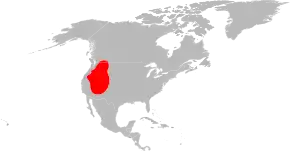

The distribution of Colorado tick fever virus is in the Rocky Mountain area of the United States at elevations between four and ten thousand feet.[7] Not surprisingly, Colorado tick fever virus can be found in places like California, Colorado, Idaho, Montana, Nevada, Oregon, Utah, Washington, Wyoming, British Columbia, and Alberta. This is roughly the same distribution as the tick that transmits the virus, shown in the adjacent picture.[5]

The virus circulates between ticks and rodents, with humans being the secondary hosts.[5] People at risk for catching the disease are hikers and campers that are in the risk areas. Also, April, May, and June are when the infections mainly occur, because this is the time when the adult ticks are prevalent in the environment. Unfortunately, this is also when the weather is pleasant for hiking and camping. The best way to avoid getting bitten and catching this disease is wearing long sleeves or pants, avoiding high tick-infested areas, and wearing tick repellent.[5]